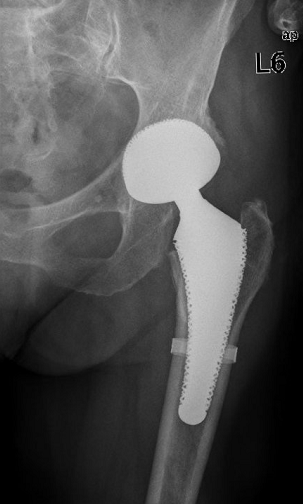

In 2002, von Salis-Soglio and Grundei developed the cementless short-stem GHEs (Figure 1 [Fig. 1]), which has a macroporous metallspongeous surface. The implant is collarless, is fully macroporous and constitutes two thirds of the length of a conventional standard shaft.

Figure 1: Orthodynamics short stem GHEs

The GHEs is titanium-niobium-coated so that implantation is possible in patients with nickel or cobalt allergy. There are 7 sizes. The surgical technique of both, femoral head resection and the medullary preparation, of GHEs are identical to those of the standard shaft. The medullary reamers are adapted to the length of the short stem. The preoperative planning is generally computer-assisted in our department. If an optimal fit of the implant is not assured during the operation, the transition to a standard shaft is possible.

Postoperatively, patients are allowed partial weight bearing (20 kg) for 3 weeks starting on the first day after surgery. After the end of the third week full weight bearing is allowed. The results of the first 55 implantations (November 2002 to December 2004) were reported in 2006 [14]. Thereafter, a subsequent analysis of 131 operations [3] showed favorable early results.